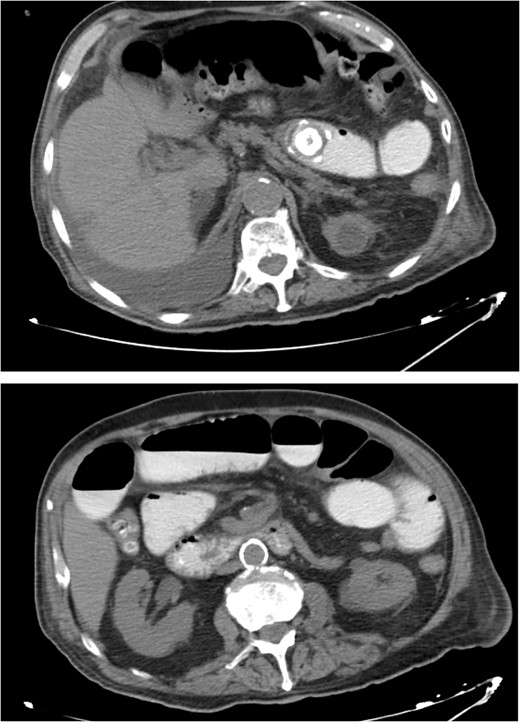

The patient was then admitted to the General Surgery department and treatment with broad-spectrum antibiotics (piperacillin/tazobactam and metronidazole) was initiated. On the second day of hospitalization, the patient underwent a repeat CT scan which indicated presence of air and oral contrast in the gallbladder, pneumobilia, swelling of the pylorus, and small bowel obstruction with the transition point being further into the ileum compared with the first CT scan (Fig. 1). Based on the comparison of the CT scan findings and past medical history of acute cholecystitis, gallstone ileus was established as the most possible diagnosis and the patient was led to the operating room.

CT images of the abdomen revealed small bowel obstruction due to gallstone and presence of air and oral contrast into the gallbladder.